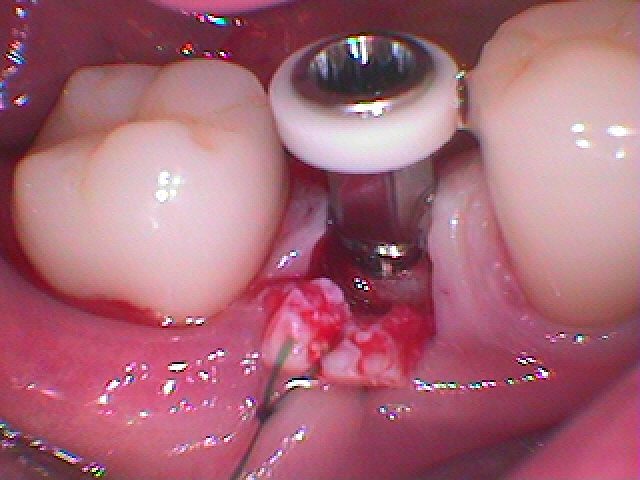

埋入時になります

角度、方向、深度、埋入位置に注意を払っています

埋入時になります